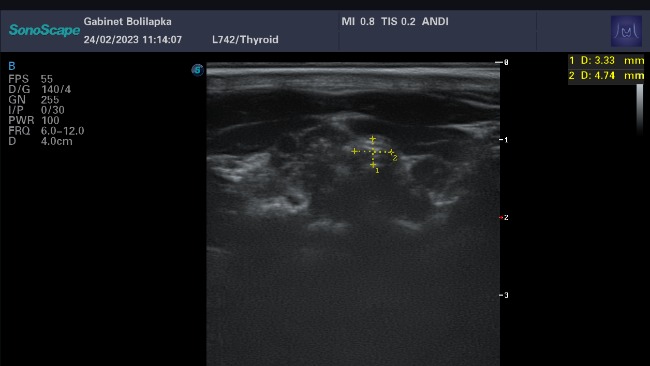

Wczoraj kolejne badania okresowe z Wampirkiem i Andusiem Wampisi całość a Andusiu tarczyca całe szczeście leczenie Andesia przebiega w normie, a Wampisiowe wyniki są w normie i suplemenciki mu bardzo pomogły za wizyte zapłaciliśmy 400 zł w tym za badania i za lekarstwo dla Andusia. Bardzo sie ciesze że ich leczenie dobrze postępuje chociaż lekarstwo nam znowu podrożało o 10 zł dlatego kolejna prośba dla was o dalsze wsparcie Buziaki ode mnie i Chłopaków <3

Oczywiście nadczynność można leczyć, Leczenie opiera się na zmniejszeniu wydzielania hormonów tarczycy (leczenie farmakologiczne lub chirurgiczne) oraz postępowaniu dietetycznym.